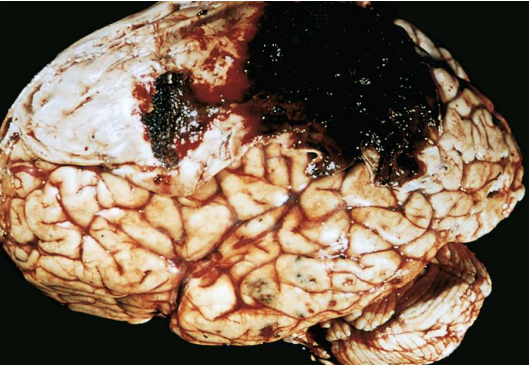

What is **spontaneous intracerebral** haemorrhage (stroke) caused by?

**Hypertension- 60 years +, rupture of small intraparenchymal blood vessels** Cerebral amyloid angiopathy Arteriovenous and cavernous malformations Tumours

39

What sites are commonly affected by spontaneous intracerebral haemorrhages?

Basal ganglia Thalamus Pons Cerebellum

40

What are the complications of spontaneous intracerebral haemorrhages?

Accumulation of hamorrhage leads to raised ICP Raised ICP causes midline shift and compression of adjacent brain parenchyma